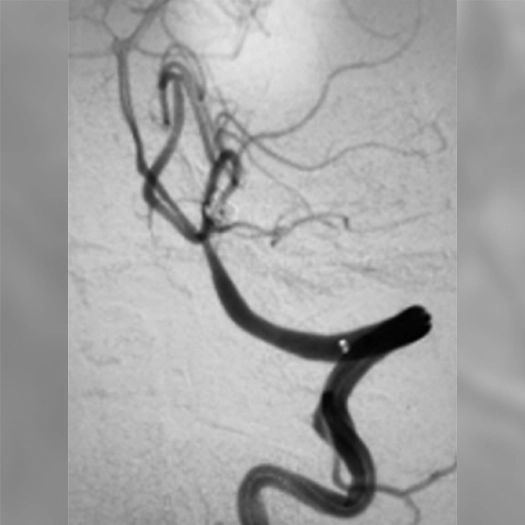

angiogram of an embolization coil place in an aneurysm

15 mm ICA terminus aneurysm coiled with PC400 and PAC400, 46% PD

Aneurysm

• PC400: optimized for aneurysm embolization

• Offered large volume with .020″ platform

• Supported by BENCHMARK family for stable access